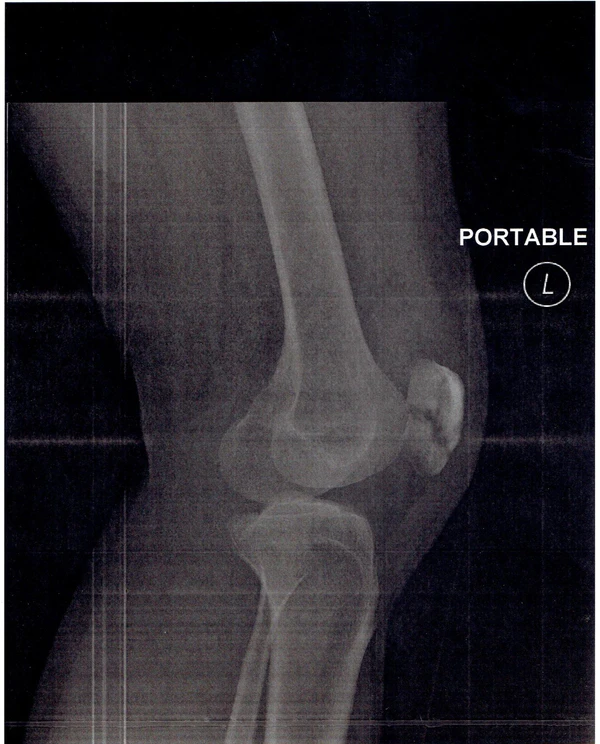

- Рентгенография коленного сустава двух проекциях

Известно множество классификаций переломов надколенника. Классификация переломов разнообразна и основана характере перелома и степени смещения его отломков. Переломы делятся на: без смещения (диастаз до 2—3 мм) и со смещением (диастаз более 3 мм или при неконгруэнтности суставной поверхности более 2 мм). Морфологически разделяют на поперечные, продольные, звёздчатые (оскольчатые) и отрывные переломы верхнего и нижнего полюсов. Также выделяют многофрагментные и остеохондральные переломы. Кроме того, выделяют открытые и закрытые переломы[3].

- Двудольный надколенник[2]